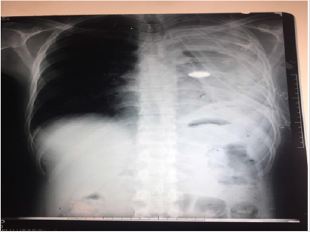

A 32-year-old male presented to OPD of Holy Family Hospital Rawalpindi with asymptomatic left sided Hemo-Pneumothorax which was diagnosed during routine occupational checkup. He had no complaints of shortness of breath or chest pain but there was a history of high-grade fever, which was on and off for 2 months, relieved by panadol. It is to be noted that there was history of similar iatrogenic pneumothorax a year ago which was treated with chest intubation for 6 days. Chest tube was removed after complete resolution of pneumothorax.On examination respiratory rate of 18 breaths per minute was noted. Palpation revealed bilateral equal chest expansion. On percussion a slightly dull note was noted on left lower lung and auscultation revealed a decreased air entry in left lower lung field. Chest X-ray showed left sided hydro pneumothorax with pleural effusion. Chest intubation was done, and patient was managed conservatively. However, he did not improve even after 10 days of chest intubation. He developed intermittent fever and became tachypnic. Therefore, thoracotomy and decortication was done. Per-op findings were Left sided fibro-thorax and thickened parietal and visceral pleura(Figure 1).

During surgery left lung was inflated and lung expansion was observed.Pleural tissue biopsy reported acute chronic inflammation with formation of granulation tissue.Unfortunately patient’s post -op xray showed collapsed left lung. Ultrasound done on 6th post-op day indicated infected fluid collection in left pleural cavity representing left sided moderate empyma. No improvement was observed on conservative management . Rethoracotomy and pleural wash was done at 25th post-op day. Perop findings revelaed clots in left pleural cavity, which were removed and decortication was done. Pleural cavity was washed with 10L normal saline. Chest tubes were placed anterior and posterior to lung. Thick piece of cortex around lung was sent for biospy which was consistent with empyma thoracis, however it was negative for granulomatous inflammation or malignancy. Post-op xray showed normally expanded left lung. The patient recovered well and was discharged.